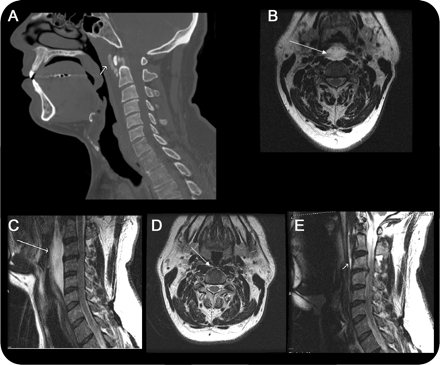

教学神经图片:急性石灰质的长肌的腱炎模仿假性脑膜炎

不寻常的急性颈部疼痛的重要原因长肌石灰质的炎